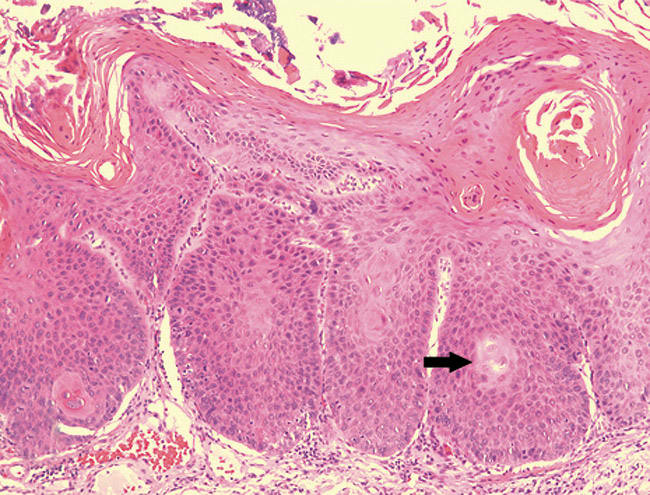

Oral epithelial dysplasia and carcinoma-in-situ

A microscopic diagnosis of epithelial dysplasia means that there are cytologic and/or epithelial architectural abnormalities. A diagnosis of dysplasia will be assigned a category—either mild, moderate or severe.16 Mild epithelial dysplasia is limited to the lower one-third of the epithelial thickness (Figure 7). Moderate epithelial dysplasia is more than one-third but less than two thirds of the epithelial thickness (Figure 8). Severe epithelial dysplasia involves more than two-thirds of the epithelial thickness (Figure 9), while carcinoma-in-situ means that the entire thickness of the epithelium is abnormal (Figure 10), although the malignant cells have not yet become locally invasive. Complicating the prediction of which lesions will undergo malignant transformation, dysplastic lesions may become invasive OCSCC without first exhibiting severe epithelial dysplasia or full-thickness carcinoma-in-situ. In a meta-analysis of pooled data from 992 patients, malignant transformation rate for mild to moderate dysplasia is estimated at 10.3%, while the malignant transformation rate of moderate to severe dysplasia is 24.1%.17